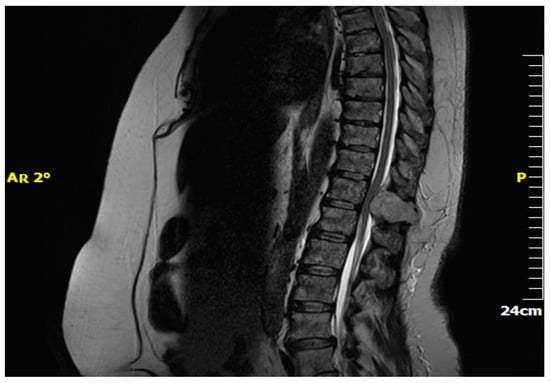

3.4. Diagnostic Evaluation